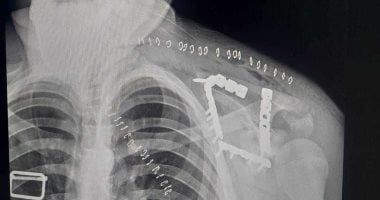

كان استقبل مستشفى التأمين الصحي بالفيوم شابًا يبلغ من العمر 17 عامًا، يعاني من كسر مفتت بعظمة لوح الكتف (Scapula)، وهي من الإصابات الدقيقة التي تتطلب مهارة عالية وتدخلًا جراحيًا متخصصًا.

خضع المريض لعملية جراحية معقدة استمرت نحو 4 ساعات تحت تأثير التخدير العام، تم خلالها رد وتثبيت الكسر بإستخدام الشرائح والمسامير.